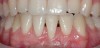

CASE 4 Fig 9. Post-orthodontic Miller Class II recession treated with surgical coverage only in spite of the incorrect inclination of the affected tooth. Clinical view immediately post-orthodontic treatment.

Figure 9

Fig 10. Same patient 5 months later showing worsening of the recession.

Figure 10

Fig 11. Same patient 1 year after connective tissue graft, showing partial root coverage.

Figure 11

It should be understood that this type of orthodontic movement requires reinsertion of a fixed orthodontic appliance in the lower arch for several months. Therefore, many of these patients reject retreatment. In such cases, surgical root coverage remains the only viable option; however, patients should be aware of the poor prognosis for complete root coverage and be prepared to accept compromised treatment outcomes (Figure 9 through Figure 11).